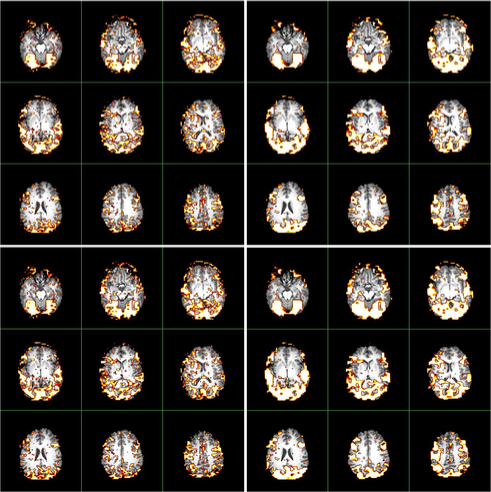

We apply the and procedures to detect activated brain regions of a simulated brain fMRI dataset, which is both spatially and temporally correlated. The experiment design, timings and size are exactly the same as those of the real fMRI dataset in Section 7.

The data are generated from a semi-parametric model similar to that in Section 5.2 of Zhang and Yu (2008). (They demonstrated that the semi-parametric model gains more flexibilities than existing parametric models.) The left panel of Figure 6 contains slices (corresponding to the 2D axial view) which highlight two activated brain regions involving activated brain voxels. The neighborhood used in the procedure is illustrated in the right panel of Figure 6.

Figure 7 compares the activated brain regions identified by the (in the left panels) and (in the right panels) procedures. Owing to the wealth of data, and for purposes of computational simplicity, results using Method I of are presented. Voxel-wise inactivity is tested with the semi-parametric test statistics (in the top panels) and (in the bottom panels) whose notation was given and asymptotic distributions were derived in Zhang and Yu (2008). The control level is . Inspection of FigureΒ 7 reveals that and locate both active regions. In particular, using the procedure, both methods detect more than voxels (which are visible when zooming the images), many of which are falsely discovered. When applying the procedure, detects voxels, whereas detects voxels. Thus the procedure reduces the number of tiny scattered false findings, gaining more accurate detections than the procedure.

As a comparison, the detection results by popular software AFNI [Cox (1996)] and FSL [Smith et al. (2004) and Woolrich et al. (2001)] are given in Figure 8. We observe that both AFNI and FSL fail to locate one activated brain area, and that the other region, though correctly detected, has appreciably reduced size relative to the actual size. This detection bias is due to the stringent assumptions underlying AFNI and FSL in modeling fMRI data: the Hemodynamic Response Function (HRF) in FSL is specified as the difference of two gamma functions, and the drift term in AFNI is specified as a quadratic polynomial. As anticipated, applying the distributions restricted to parametric models to specify the distributions of test statistics in AFNI and FSL leads to bias, which in turn gives biased calculations of -values and -values. In this case, the detection performances of both the and procedures deteriorate, and the procedure does not improve the performance of the procedure. See Table 3 for a more detailed comparison.